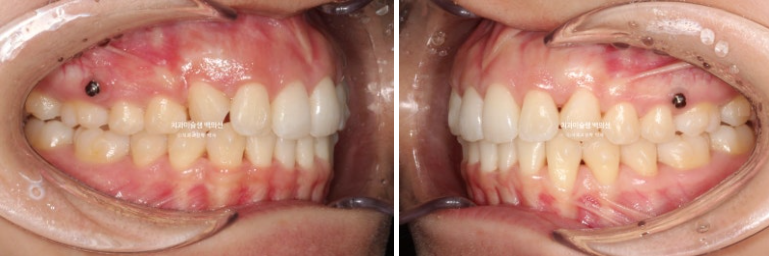

23.09~25.09

2년 전 23년 9월 약간의 돌출과 입술부전증 치료를 위해 오신 환자분입니다.

23.09

앞니가 삐뚠 부분이 있습니다.

환자분은 발치교정은 원치 않았기에 치료계획은 사랑니 발치하고 사랑니 공간으로 어금니를 밀어 앞니를 가지런히 펴고 뒤로 넣는 계획입니다.

인비절라인 치료를 선택하셨고